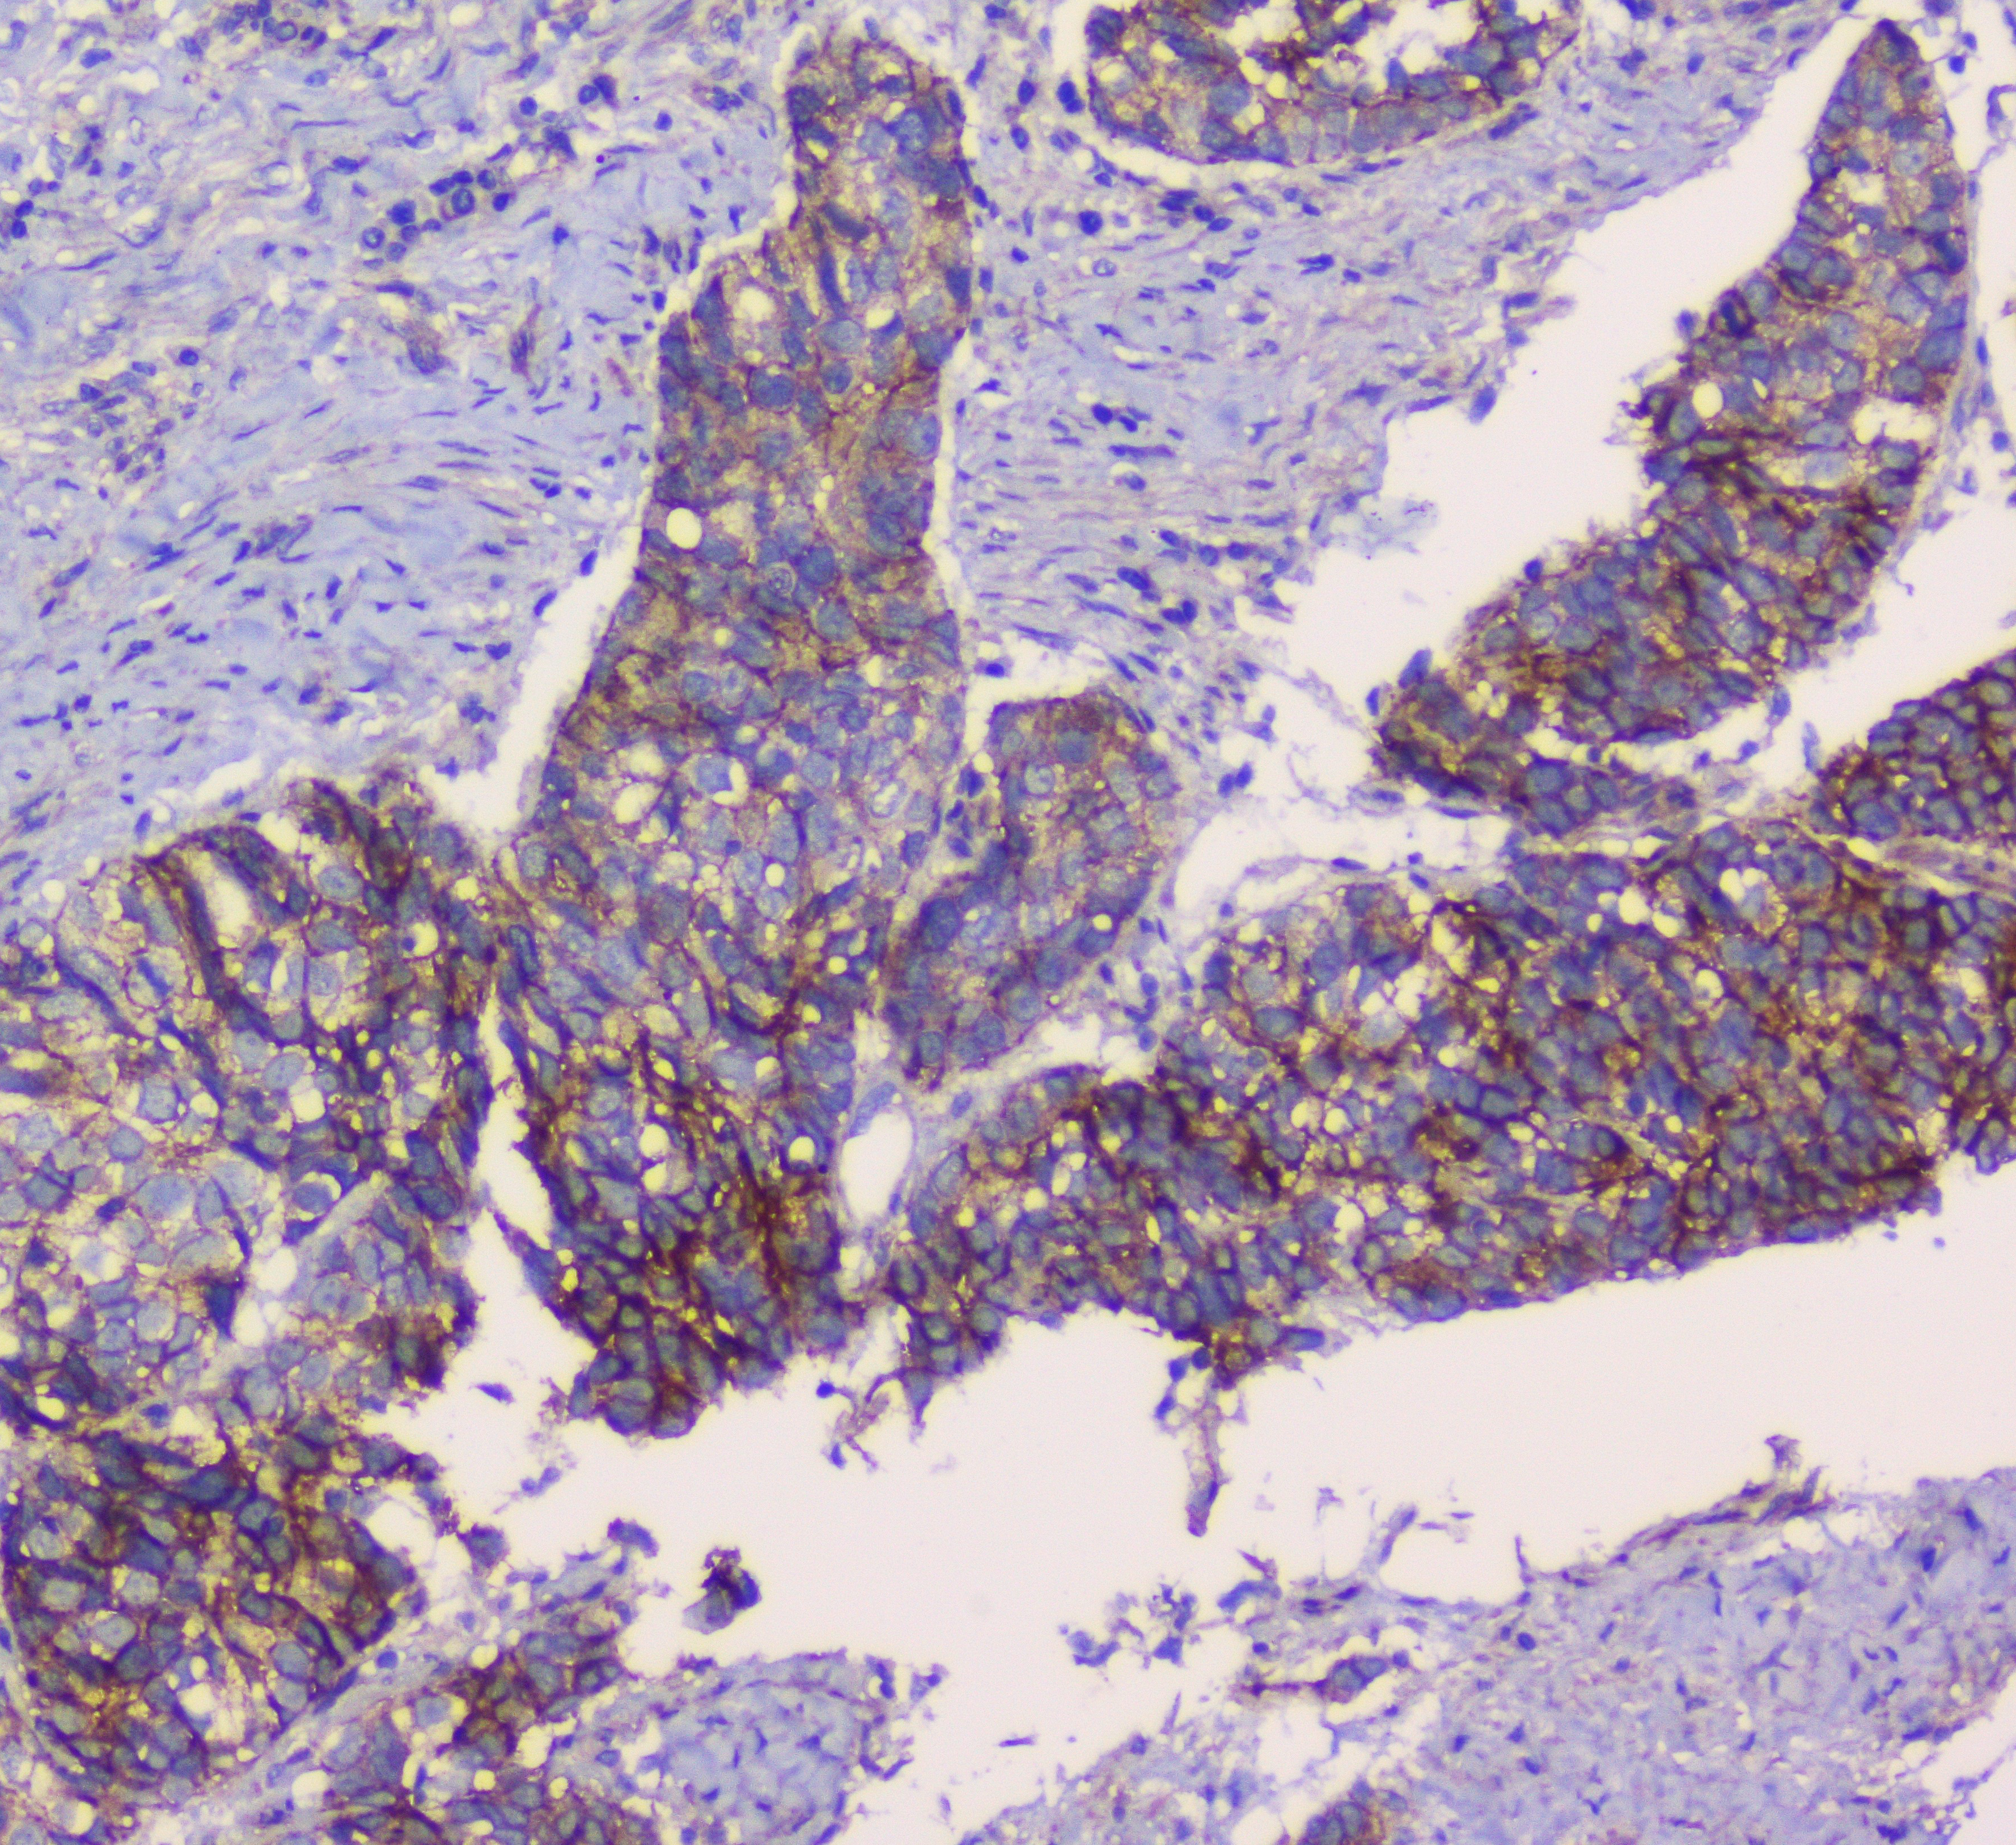

Produktinformationen "Anti-beta Catenin"

Protein function: Key downstream component of the canonical Wnt signaling pathway. In the absence of Wnt, forms a complex with AXIN1, AXIN2, APC, CSNK1A1 and GSK3B that promotes phosphorylation on N-terminal Ser and Thr residues and ubiquitination of CTNNB1 via BTRC and its subsequent degradation by the proteasome. In the presence of Wnt ligand, CTNNB1 is not ubiquitinated and accumulates in the nucleus, where it acts as a coactivator for transcription factors of the TCF/LEF family, leading to activate Wnt responsive genes. Involved in the regulation of cell adhesion, as component of an E- cadherin:catenin adhesion complex. Acts as a negative regulator of centrosome cohesion. Involved in the CDK2/PTPN6/CTNNB1/CEACAM1 pathway of insulin internalization. Blocks anoikis of malignant kidney and intestinal epithelial cells and promotes their anchorage-independent growth by down-regulating DAPK2. Disrupts PML function and PML-NB formation by inhibiting RANBP2-mediated sumoylation of PML (PubMed:17524503, PubMed:18077326, PubMed:18086858, PubMed:18957423, PubMed:21262353, PubMed:22647378, PubMed:22699938, PubMed:22155184). Promotes neurogenesis by maintaining sympathetic neuroblasts within the cell cycle. [The UniProt Consortium]

| Anwendung: | FC, ICC, IF, IHC (paraffin), WB |

| Spezies-Reaktivität: | human, mouse, rat |

| Immunogen: | Recombinant protein corresponding to A2-K233 of Human beta Catenin |